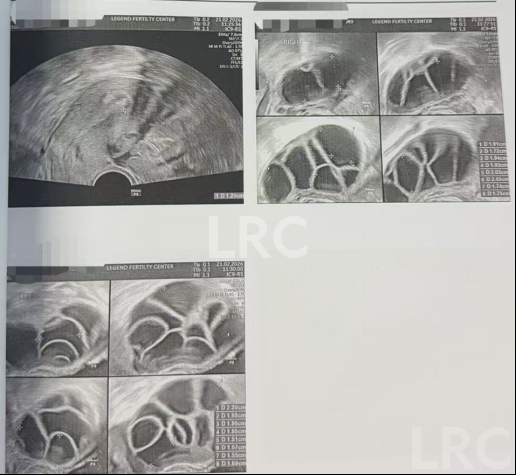

取卵及受精

取卵:15颗

成熟MII:10颗

ICSI受精:10颗

养囊成功:10颗

▲ C女士的养囊报告